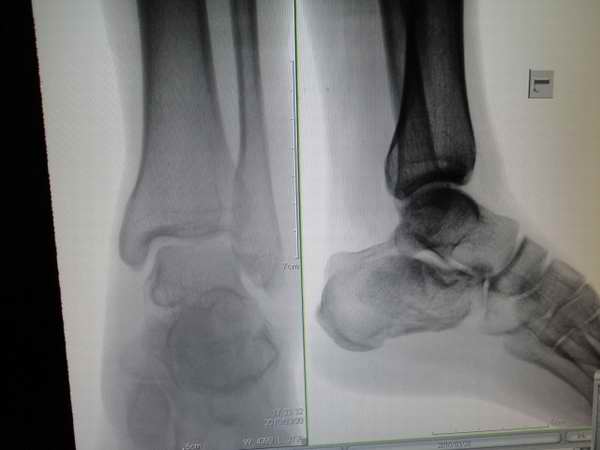

以下是引用黑白光影在2010-4-10 20:37:00的发言:[br]跟骨骨折。外踝也可能有骨折(外踝软组织很肿),距骨内侧有可能是楼主说的是重叠影也有可能是撕裂性骨折,只是在屏上翻拍片子不清楚。

以下是引用眼睛在2010-4-11 7:04:00的发言:[br]跟骨骨折比较明显,距骨改变同意重叠影一说。

以下是引用zhanggenliang在2010-4-10 21:26:00的发言:[br]跟骨骨折,此片不能诊断外踝骨折,可以说可疑,距骨内侧支持楼主重叠影一说。可以ct检查,也可以过几天血肿吸收后复查